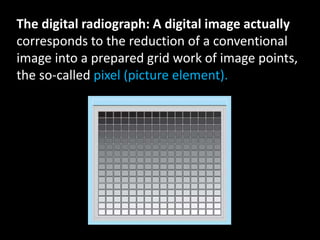

4. Digital radiography provides advantages like automated measurements and image manipulation but has higher initial costs and bulkier sensors.